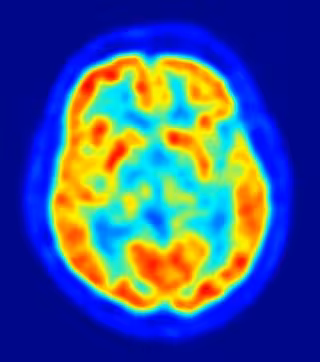

Un mecanismo previene alteraciones en la formación de neuronas durante el desarrollo embrionario

Un equipo multidisciplinar del Consejo Superior de Investigaciones Científicas (CSIC) en colaboración con científicos de la Universidad de Barcelona ha descubierto un mecanismo que previene alteraciones en la formación de neuronas, un proceso denominado neurogénesis, durante el desarrollo del sistema nervioso de los vertebrados.

La inhibición lateral durante el desarrollo embrionario tiene como objetivo controlar el número de neuronas que se forman. Consiste en células que inhiben a otras adyacentes, favoreciendo así su propia diferenciación en neuronas.

"Las células precursoras de neuronas con mayores niveles de proteínas de membrana llamadas Delta inducen señales inhibitorias en las células precursoras adyacentes, que ven entonces reducido su nivel de Delta y, por tanto, promueven la diferenciación neuronal de las primeras. De este modo, se evita la generación masiva de neuronas y se facilita la producción ordenada de los innumerables tipos neuronales necesarios para la función cerebral", explica el investigador del CSIC Saúl Ares, que trabaja en el Centro Nacional de Biotecnología (CSIC).

Este estudio se ha llevado a cabo gracias a un modelo teórico?computacional de la retina, mediante el cual los científicos han comprobado que la inhibición lateral, un proceso que regula la generación de neuronas en el sistema nervioso central, sufre alteraciones en los frentes neurogénicos. "Estos marcan la frontera entre las regiones que están generando neuronas y las zonas vecinas, en las que aún no ha comenzado la neurogénesis", explican.